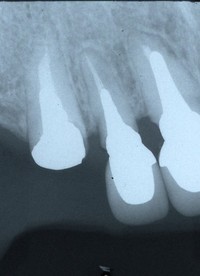

20〜39歳の歯やお口のチェックポイント

20〜39歳の歯やお口のチェックポイント 40歳から65歳のアンチエイジング歯科チェックポイント

40歳から65歳のアンチエイジング歯科チェックポイント